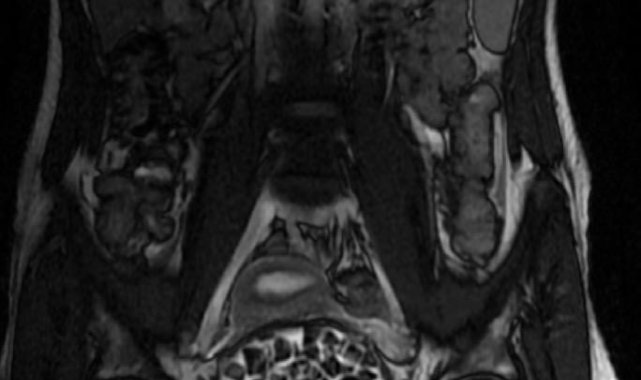

Hastasının durumuna yönelik konuşan Üroloji Uzmanı Doç. Dr. Erkan Erkan, "Hastamızın 2004 yılında doğduğunu ardından doğar doğmaz ekstrofi vezika dediğimiz 50 binde bir görülen bir anomaliden dolayı art arda ameliyatlar geçirdiğini öğrendik. 10 yaşında yine bir ameliyat geçirmişti, gerekli görüntüleme ve tetkiklerimizi yaptırdık. Normalde mesanesinin olması gereken yerin hemen arka kısmında taşlarla dolu bir kese olduğunu gördük, bunun üzerine ek görüntülemeler; MR çektirdik. Hastamız çelişkili açıklamalar almıştı, kendi radyolojik kliniğimiz ve edindiğimiz konsültasyonlarda taşların mesanede değil vajinal boşlukta oluştuğunu düşündük, bir planlama yaptık. Kadın doğum hocamızın da çabasıyla taşları tamamen temizledik ardından ileride normal bir hayat sürmesi bakımından oraya plastik cerrahi yaptık. 287 adet taş çıkardık, pratikte gerçekten görünce çok şaşırdık çünkü bu aynı zamanda literatürde çok nadir görülen bir olay. Biz ameliyata hazırlanırken de teorik olarak biraz araştırdık. Literatürde gördüğümüz kadarıyla buna benzer bu tanıma uyan bir vaka vardı. Literatürde sanırım yayınlanmış 2'nci vaka olacak. Farkındalık çok önemli, bilinçli bir hastamız vardı. Doğumsal anomaliyle doğan çocuklarımızda ileride bunlara bağlı bazı sıkıntılar çıkabileceğinin öngörülmesi lazım. İlgili tedavilerini alsalar bile düzenli takiplere gelmeleri gerekiyor. İleride eğer dikkat etmezse ki zannetmiyorum, tekrarlayabilir. Bu rahatsızlık ekstrofi vezikal epispadias durumu çok nadir bir durum" dedi.

Genç kızın uzun süredir devam eden karın ağrısı olduğunu söyleyerek sözlerine başlayan Jinekolojik Onkoloji Uzmanı Op. Dr. Emin Erhan Dönmez, "Mesane taşları olduğu düşünülerek daha büyük bir hastaneye refere edilmiş. Aramızda mini bir konsey yaparak muayene ettik. Vajen bir hazne görevi görerek orada durağan bir idrar, uzun süre beklediği için idrar içindeki minerallerde çökerek taşlar oluşmuş. Mesanedeki idrarın vajene akmış olabileceği ve vajende göllenen idrar nedeniyle taşların burada oluşacağını düşündük, ameliyatımızı planladık. Ameliyata tanı amaçlı girmiştik, sistoskopi (Mesane gibi idrar yollarını kapsayan kısımlardaki rahatsızlıkların teşhis ve tedavisinde kullanılan endoskopik bir yöntem) dediğimiz ameliyatı Erkan Hocam ile birlikte gerçekleştirdik. Önce mesaneyi bir görüntüledik, mesane tabanına yaklaşık 2-3 cm'lik bir alandan vajene fistülize olduğunu gördük. Mesaneden vajene geçtiğimiz esnada tüm vajenin taşlarla dolu olduğunu gördük. Tanı amacıyla girdiğimiz ameliyatta her şey de olağan gittiği için tedaviye geçtik. Taşların çıkabileceği kadar bir genişlik sağladık. Daha sonra yaklaşık en büyüğü 2,5 cm boyutlarında olan, irili ufaklı 287 tane taşı ameliyat esnasında çıkarmış olduk. Taşların tekrarlamaması için idrarın göllenmemesi, en azından dışarıya rahatça boşalabilmesi için vajinal rekonstrüksiyonu sağladık. Ameliyatta da herhangi bir problem yaşamadık. Literatürü Erkan Hocam ile birlikte değerlendirmiştik. Primer olarak vajende birikmiş olan bu kadar çok sayıda taşla ilgili bir makale görmedik, rastlamadık" dedi.